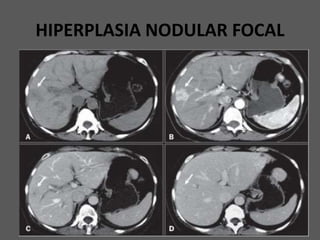

HIPERPLASIA NODULAR FOCAL